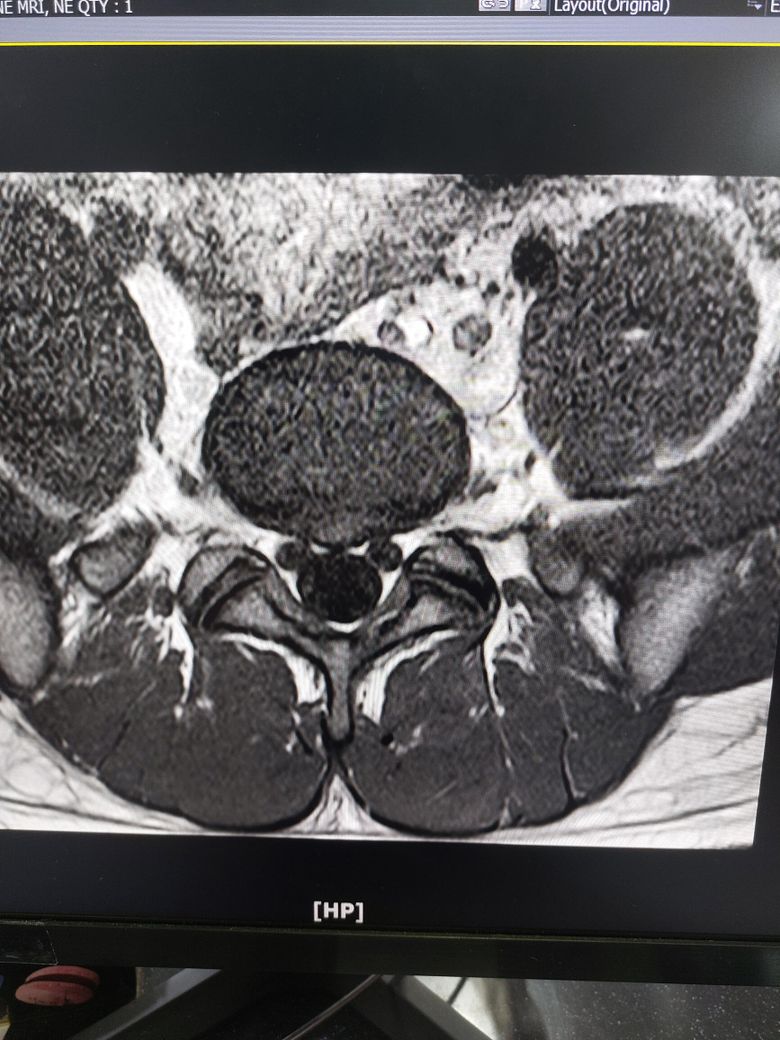

허리디스크 심한편인가요? [Mri 사진 첨부]

멸개월전부터 요추가 뻣뻣하고 시큰거리다가 최근에 좀 나아지긴 해도 만성적이라서 오늘 mri 찍고 허리디스크 진단받았습니다

(요추 맨 밑 천추 위 디스크)

Mri 찍은 병원은 고주파 시술같은거 하라고 하고 다른병원은 이정도면 잘 쉬면 완치된다고 하는데

1. 이정도면 아직 팽윤단계인가요?

1. 이정도면 아직 팽윤단계인가요? 디스크 자체도 심하지 않을 뿐더러 그에 따른 증상인지 여부도 확실하지 않습니다